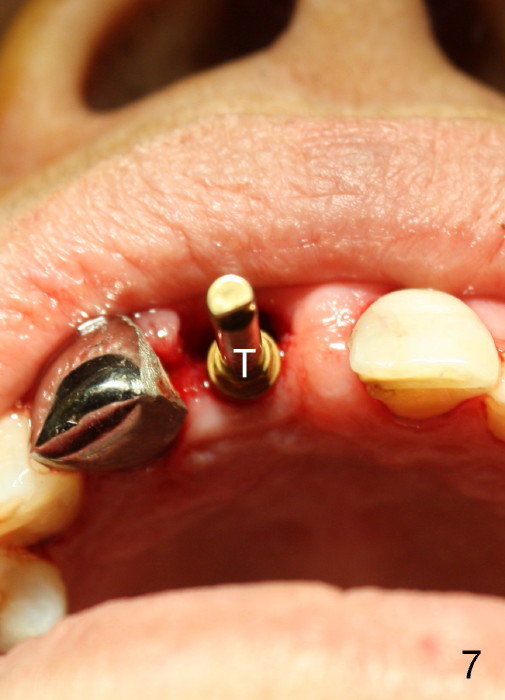

A 64-year-old lady requests replacing #7 and 8 crowns (Fig.1,2). When #8 is extracted, the labial plate is found to be missing (Fig.3). Following 2 mm pilot drill (Fig.4,5 P), 3.8 mm tap drill (Fig.6,7 T) and 4.5x14 mm implant (Fig.8 I) and 4.8 mm abutment (Fig.9 A), corticocancellous bone is harvested from the left tuberosity and placed in the labial gap of the socket (Fig.10 G). Collagen dressing is placed over the bone graft (Fig.11 C). The former is secured in place by an immediate provisional (P).